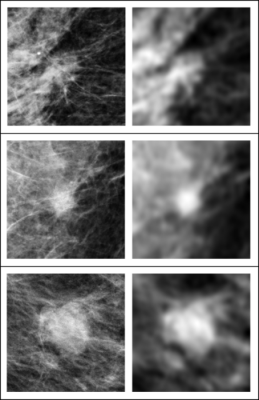

In these three examples of soft tissue lesions, the images are unperturbed on the left column and blurred on the right column. The AI system was sensitive to the blurring, while the radiologists were not. This showed that the AI system relies on details in soft tissue lesions that are considered irrelevant by the radiologists. Image courtesy of Taro Makino, NYU’s Center for Data Science

More specifically, while radiologists primarily relied on brightness and shape, the DNNs used tiny details scattered across the images. These details were also concentrated outside of the regions deemed most important by radiologists.